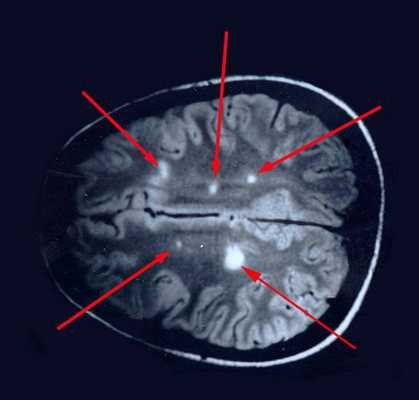

При вероятном РС, наряду с полным неврологическим осмотром, необходимо проводить исследование головного и спинного мозга при помощи МРТ. Этот способ исследования является наиболее информативным дополнительным методом диагностики. С его помощью можно обнаружить участки изменённой плотности в белом веществе головного мозга (очаги демиелинизации и глиоз). [10]